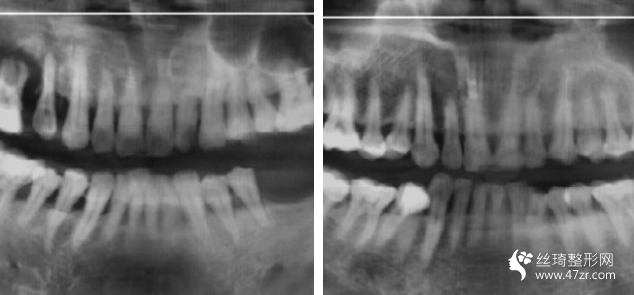

3.長沙優(yōu)享新天地口腔門診部張思齊執(zhí)業(yè)醫(yī)師案例展示

這種植牙終于完全好了,特別開心,試著吃一些軟食物,我已經(jīng)很久沒有用左邊咀嚼過東西了,過程不疼的!麻藥打好!半個(gè)小時(shí)就好了!今年年頭裝的牙!用到現(xiàn)在了!很牢固!植入種植體,修復(fù)一段時(shí)間就可以戴牙冠了

關(guān)于牙齒的調(diào)節(jié)修復(fù)方案,因?yàn)閭€(gè)人情況各異,并沒有統(tǒng)一的固定模式,對(duì)于我們自己來說是好的,能夠接受就好,具體的還需要在線咨詢,讓醫(yī)生問我們一個(gè)合理的方案。 以后必須學(xué)會(huì)護(hù)理、保護(hù)好我們的牙齒才對(duì),無論是真牙,還是假牙。